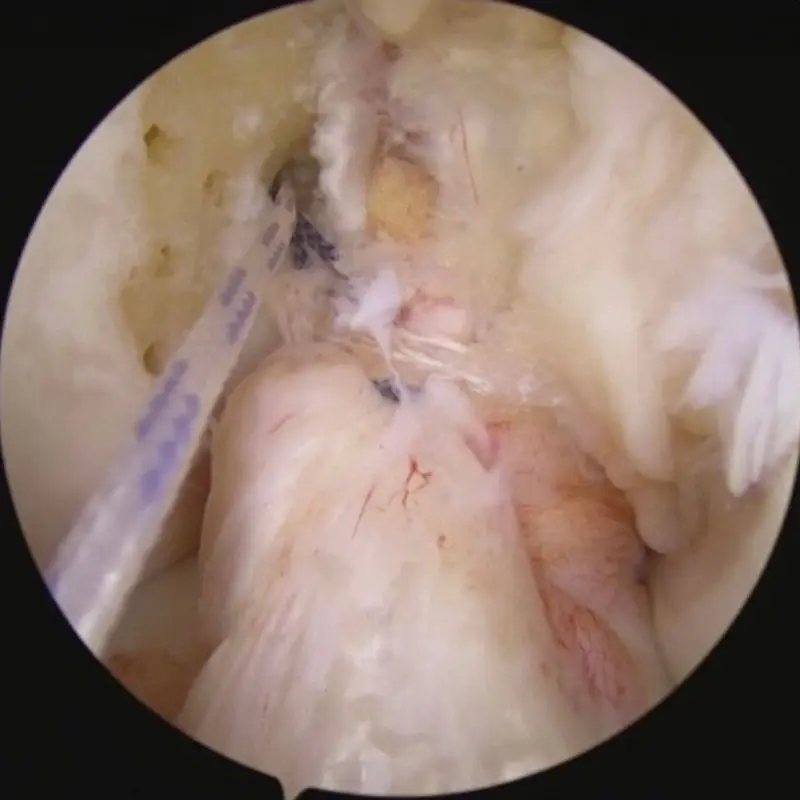

Final product with Internal Brace suture tapes in place before insertion of BEAR implant.